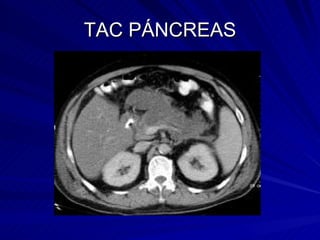

TOMOGRAFIA COMPUTADA HALLAZGOS PANCREATITIS AGUDA: Crecimiento de la glándula Pérdida de nitidez o claridad de sus bordes Hipodensidad de su parénquima

TOMOGRAFIA COMPUTADA La TAC. es el estudio de oro para el diagnóstico de: Pancreatitis aguda y gran apoyo para el diagnóstico de Pancreatitis crónica.

TOMOGRAFIA CONPUTADA HALLAZGOS EN PANCREATITIS CRÓNICA Obstructiva Calcificante: Calcificaciones conducto pancreático Dilatación de conductos secundarios Hipodensidad de conductos secundarios

TAC PÁNCREAS